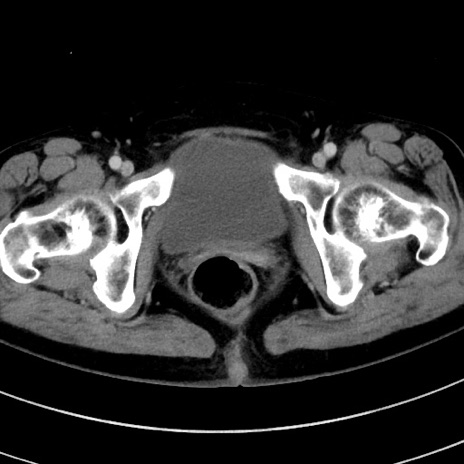

症例9(横断像)

【症例】 60歳代女性

【主訴】むかつき、みぞおちの痛み

【現病歴】3日前よりむかつきがあり、食事がとれない。

【既往歴】糖尿病

【身体所見】発熱なし、心窩部圧痛軽度あるも、腹膜刺激症状なし。

【データ】WBC 7400、CRP 1.92